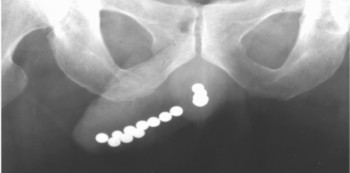

The urologist, however, found 39 magnetic beads, in his urinary tract. The child confessed to putting the beads inside his penis because he was “curious”.

Thankfully, in this case, they managed to remove the beads through surgery, and the child is able to urinate once again.

Radiological tests are necessary to determine the exact size, number and nature of the foreign object(s). Treatment involves diagnosing complications, foreign body extraction, and avoiding compromise of erectile function.